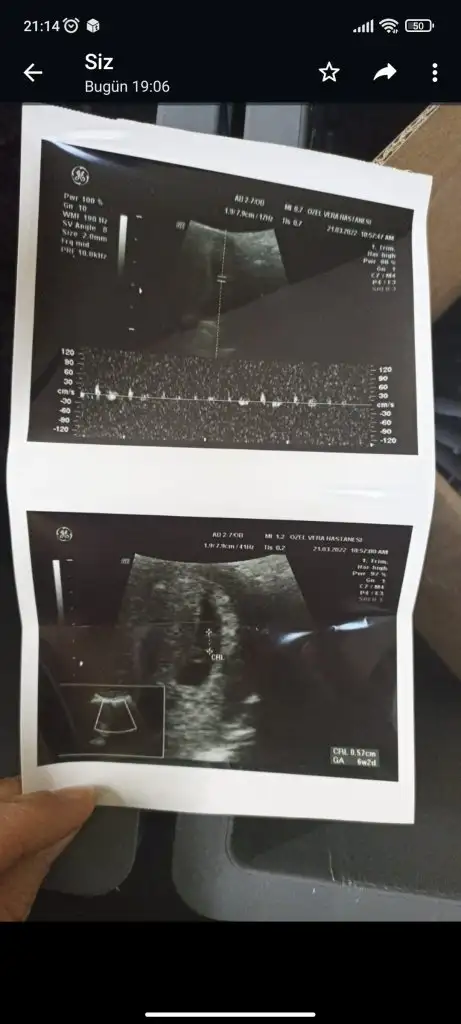

Benm 6+2 haftalik. Karından ultrasondan bakıldı. Bende merak ettim. Tahminin nedirSelam Kızlarbir çok kişi gruplardan beni bilir. Yine yetiştim imdatlara

kuzucum maşallah minicikBenm 6+2 haftalik. Karından ultrasondan bakıldı. Bende merak ettim. Tahminin nedir

kuzu bu erkek gibi duruyor öğrenince yaz olur muKarından ultrason 11+4